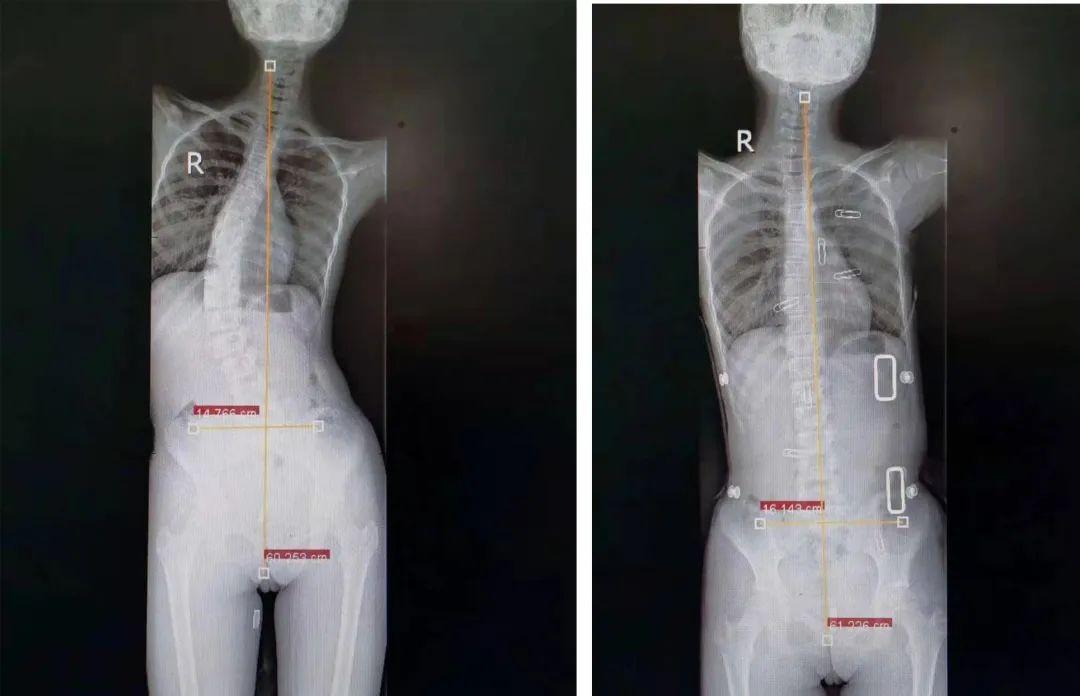

姓名:刘某某 性别:女性 年龄:19岁 主诉:发现脊柱侧弯5年,加重并胸

女生的脊柱就能够基本像正常人一样直,能够正常生活了,只要脊柱侧弯